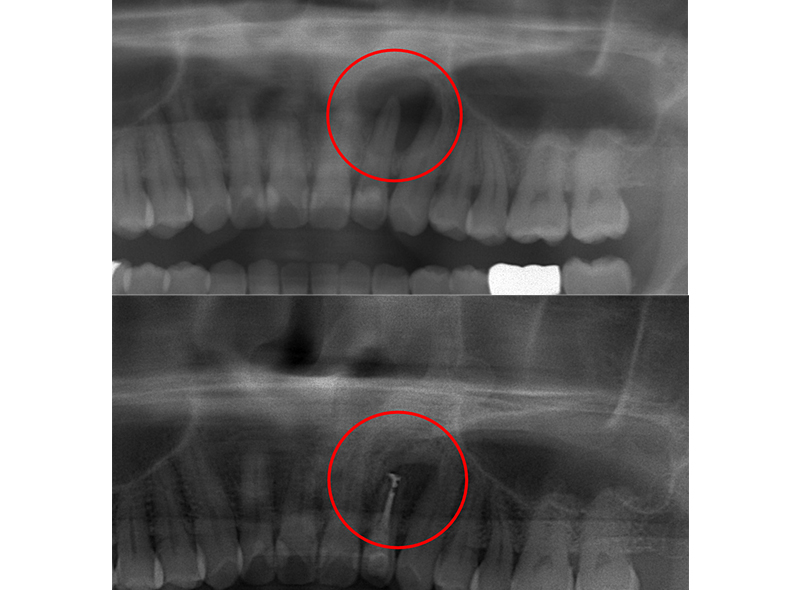

歯根端切除術とは、精密根管治療における外科的処置(歯内療法外科)の一つです。根管治療終了後に、一定の期間経過観察を行っても治癒の傾向が見られない場合に、続きの処置として、歯内療法外科を適応するケースがあります。

歯根端切除術などの歯内療法外科は、根尖と病変を摘出することで、予後不良の根尖性歯周炎を治癒させ、歯を抜かずにする治療です。

検査・診断

レントゲン検査を行い治療ができるかを診断します。どの歯根のどの場所にどんな原因があるのかを見極めることが重要です。

治療方針として根管治療、歯根端切除術、再植術、抜歯の選択判断も重要となります。手術法、リスク、経過などの説明をして治療日を予約します。 -

経過観察

術後2か月、6ヶ月、1・2年後に定期経過観察を行い、症状やレントゲンで病変の影をチェックし治癒・再発を確認します。遠地の方は地元かかりつけ歯科で定期検診でも可能です。

再発の場合は術後1か月前後に腫れや痛み、フィステルが出てくることが多く、それがなければ成功へと向かいます。完治の確認は手術1年後の症状とレントゲンです。